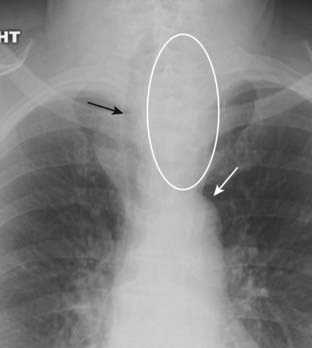

image Substernal goiters characteristically displace the trachea either to the left or right above the level of the aortic arch, a tendency the other anterior mediastinal masses do not typically demonstrate. Classically, substernal goiters do not extend below the top of the aortic arch (Fig. 12-2).

image

Figure 12-2 Substernal thyroid mass.

The lower pole of the thyroid may enlarge but project downward into the upper thorax (white oval) rather than anteriorly into the neck. Classically, substernal thyroid goiters produce mediastinal masses that do not extend below the top of the aortic arch (solid white arrow). Substernal goiters characteristically displace the trachea (solid black arrow) either to the left or right above the aortic knob, a tendency the other anterior mediastinal masses do not typically demonstrate. Therefore, you should think of an enlarged substernal thyroid goiter whenever you see an anterior mediastinal mass that displaces the trachea.

imageTherefore, you should think of an enlarged substernal thyroid whenever you see an anterior mediastinal mass that displaces the trachea.